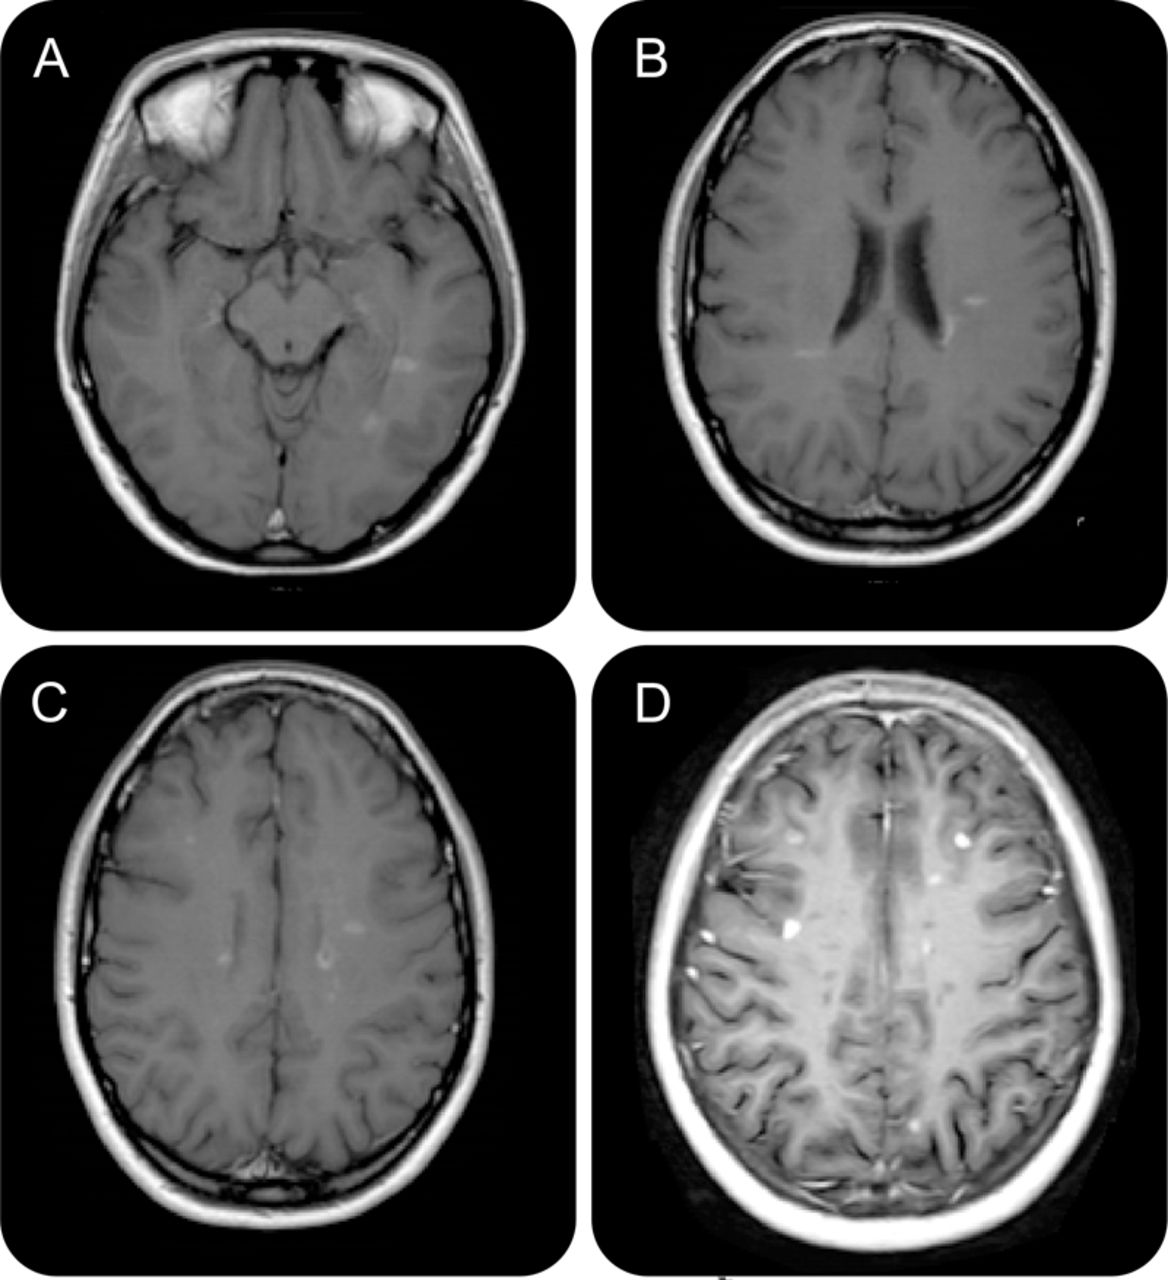

病人经历,然而,严重的女士复活16天(病人1),19天(病人2),和fingolimod启动后6天(病人3)。血细胞计数fingolimod启动显示预期的淋巴细胞减少(1 - 2周后患者1:480年淋巴细胞/毫升;病人2:520年淋巴细胞/毫升;患者3:550淋巴细胞/毫升)。患者1经验眼球震颤、步态共济失调和正确的肢体感觉障碍。患者2和3呈现严重的轻偏瘫,病人3 hemi-hypesthesia和构音障碍有关。eds增加1周患者1中从2.0到4.0,在病人2从1.5到5.5,从2.0到5.0病人3。大脑核磁共振扫描,执行临床复发发作后2 - 7日天,显示新T2损伤和8 Gd + 28 T1病变患者1,11个新的T2病灶和至少6 Gd + T1病变病人2 (图),重新激活和尺寸增加的内囊损伤的病人3。